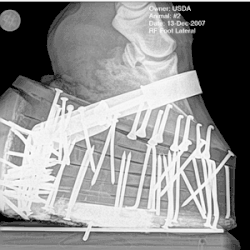

Performance horses, sometimes called "padded" or "built up", exhibit flashy and animated gaits, lifting their forelegs high off the ground with each step.[25] This exaggerated action is sometimes called the "Big Lick".[26] The customary style for rider attire and tack is saddle seat. Horses are shod in double and triple-nailed pads,[25] which are sometimes called "stacks".[27] In the early 21st century, this form of shoeing is now prohibited at shows governed by the National Walking Horse Association (NWHA),[22]: 3 and the United States Equestrian Federation (USEF).[28] Artificially set tails are seen in "performance" classes, on full-grown horses in halter classes, and in some harness classes, but generally are not allowed in pleasure or flat-shod competition.[24]: 12